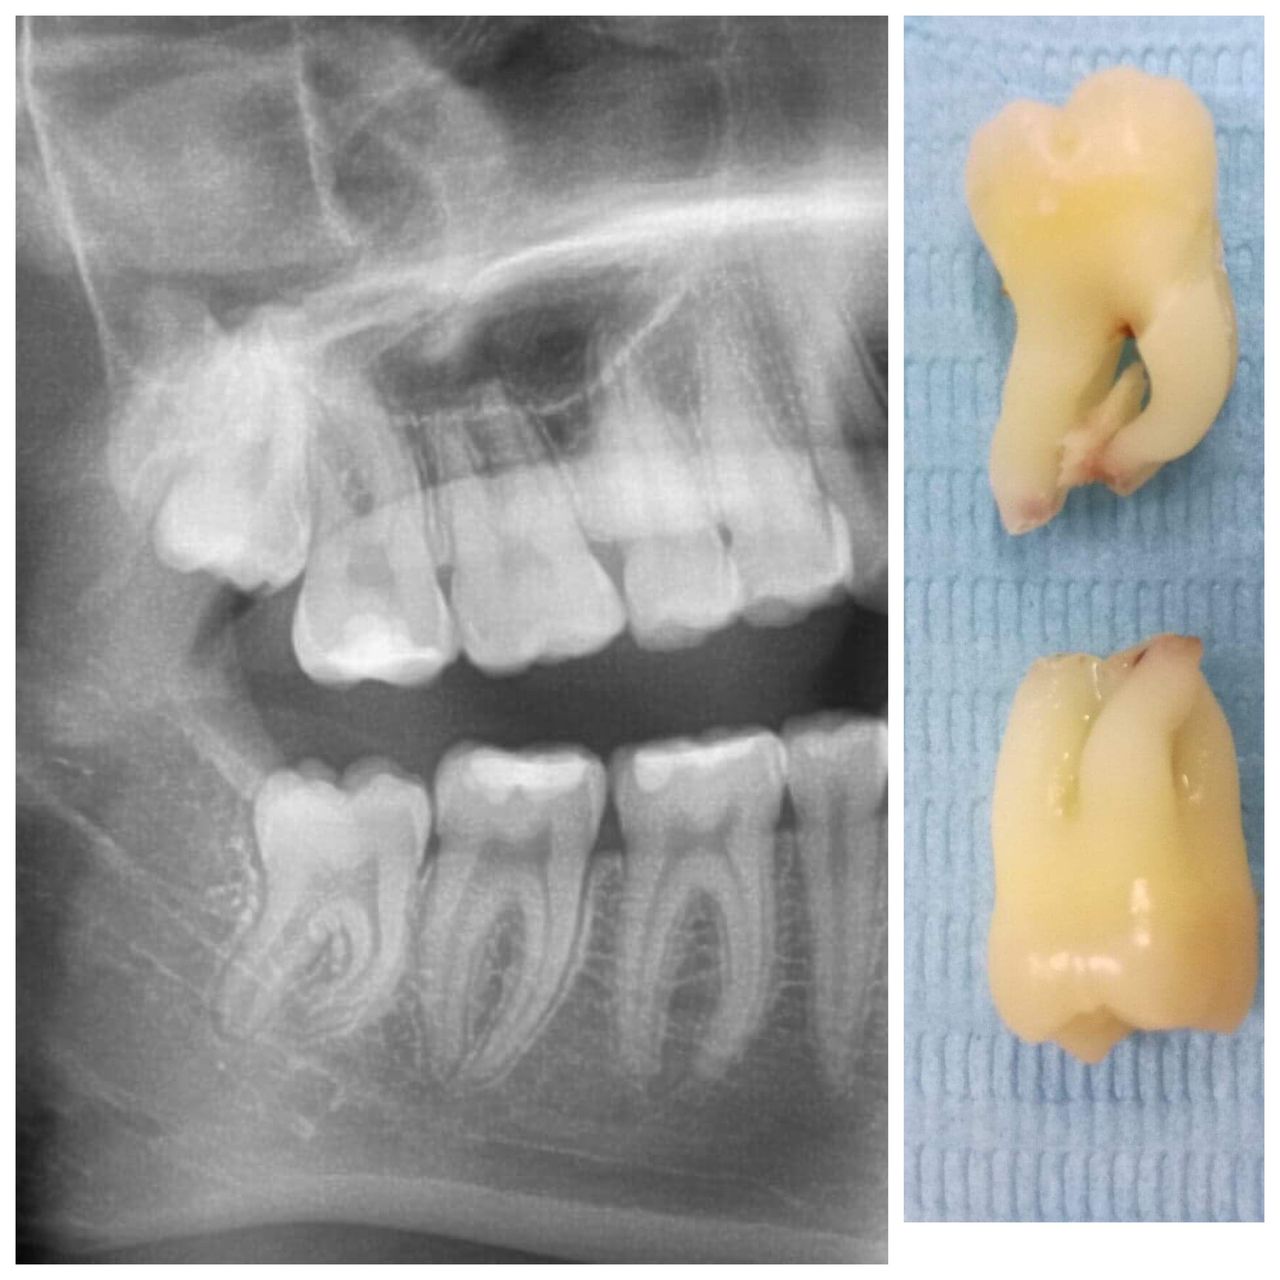

Mam duże doświadczenie w usuwaniu zębów zatrzymanych i leczeniu implantologicznym.

- Zęby zatrzymane